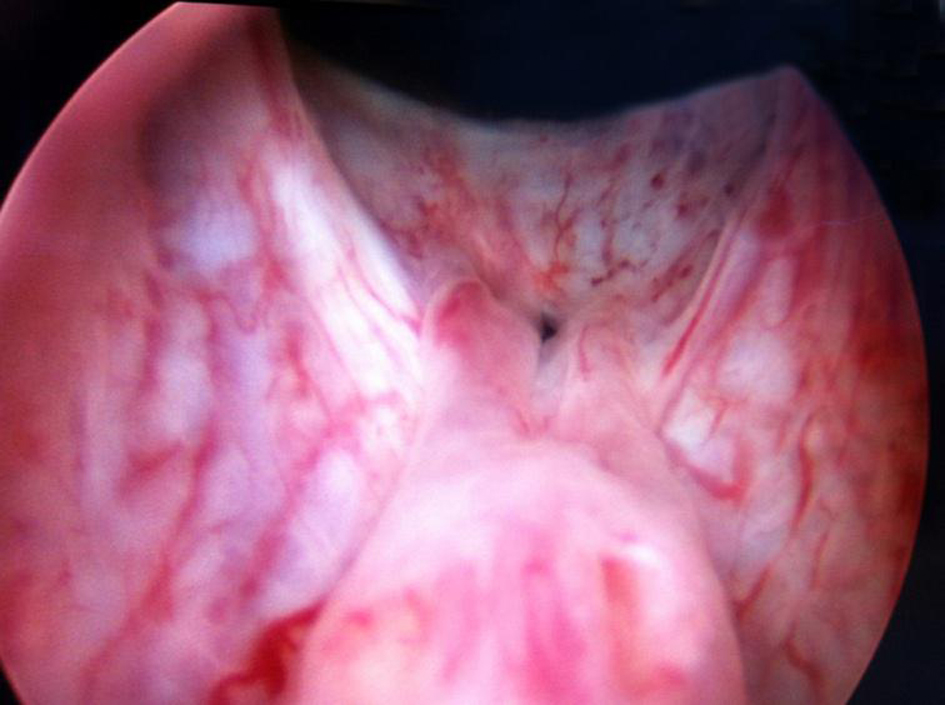

Cystourethroscopy revealed bilateral ectopic ureters opening into prostatic urethra just proximal to the verumontanum. Left ureteric opening was patulous (Fig. 4). Right ureterocele was visible in the empty bladder with a dimple of stenosed opening and this ureterocele was overlapping and obstructing the left ureteric opening (Fig. 5). Right ureterocele got effaced on distending the bladder and bladder neck was wide open. Trigone was absent. Urinary bladder was of normal capacity, congested and mildly trabeculated. Ureteroscope when passed into left patulous ureteric opening led to dilated tortuous left ureter. Right ureteric opening could not be identified.

![]() Click for large image | Figure 4. Left patulous ureteric opening with effaced right ureterocele. |

![]() Click for large image | Figure 5. Right sphincterostenotic ureterocele visible in empty bladder. |

In this case the ectopic ureterocele was missed on ultrasonography, CT and MRI abdomen but was obvious on cystourethroscopy in the empty bladder and got effaced on distending the bladder, so concurrent endoscopic evaluation is important for final diagnosis and operative intervention. The ureterocele was incised longitudinally over the stenosed orifice with Collins hot knife and double J stent was placed to improve renal functions.